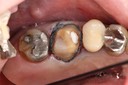

Wayne Chin #14 finish